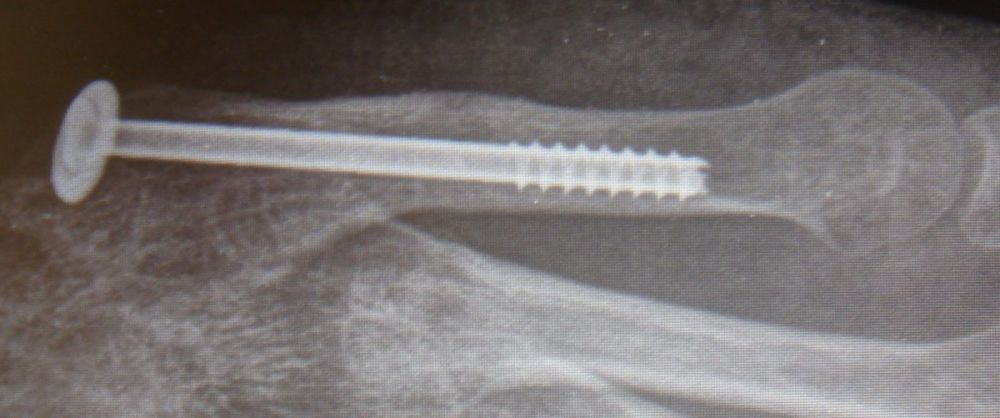

2. Atrophic nonunion 5th metatarsal (Jones fracture) of the left foot in a 25-year-old male.

Treatment: Percutaneous fixation with a screw and using specific grafts

I. Before surgery, anteroposterior x-ray of the foot II. Four months post-surgery with union of the fracture and patient is walking without pain.